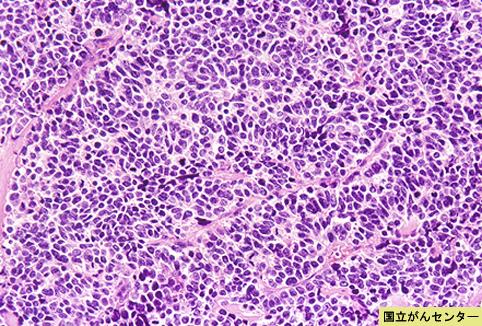

Criteria of Hist.ClassificationMalignant epithelial tumor/Undifferentiated carcinoma

LocationLarge intestine(Colon)/Ascending colon

Technique, MethodHistology

Macroscopic TypesType 5 Unclassfied type/

Size40 -

Depth of Tumor Invasionserosa (adventitia)